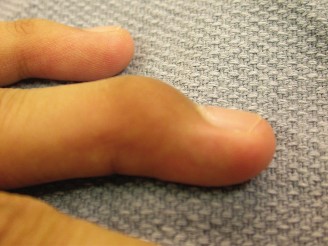

CASE 8 A 17-year-old male sustained an injury to his middle finger while catch…

CASE 12 A 24-year-old, law student injured her left index finger during a volle…